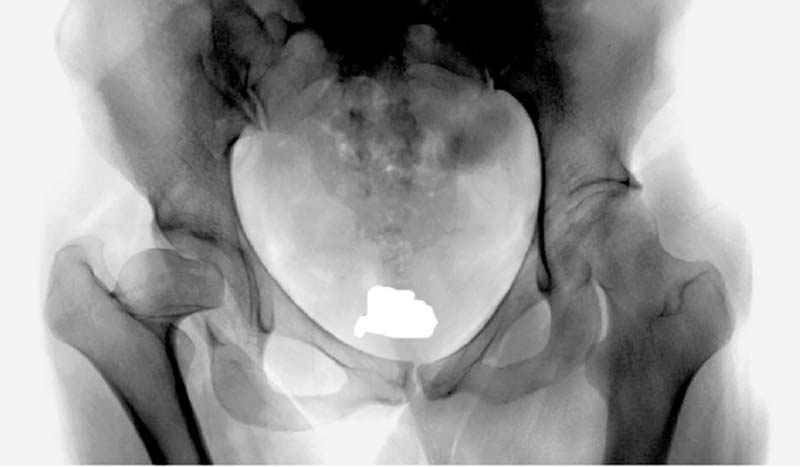

Рис.1 Трехмерная модель тазобедренного сустава с аналогом связки головки бедра. Заметно, что из торца головки выходит капроновый шнур, который с одной стороны прикрепляется к ножке бедренной части модели, а другой его конец, проходя через головку и прикрепляется к вертлужной части модели. Динамометр оказывается не нагруженным, так как аналог связки головки бедра замыкает подвижный узел модели во фронтальной плоскости.

|

Рис.2 Та же трехмерная модель тазобедренного сустава без аналога связки головки бедра. Пружина динамометра удерживает тазовую часть модели от опрокидывания, поддерживая стабильность так же, как отводящие мышцы обеспечивают ее в отсутствии связки головки бедра.